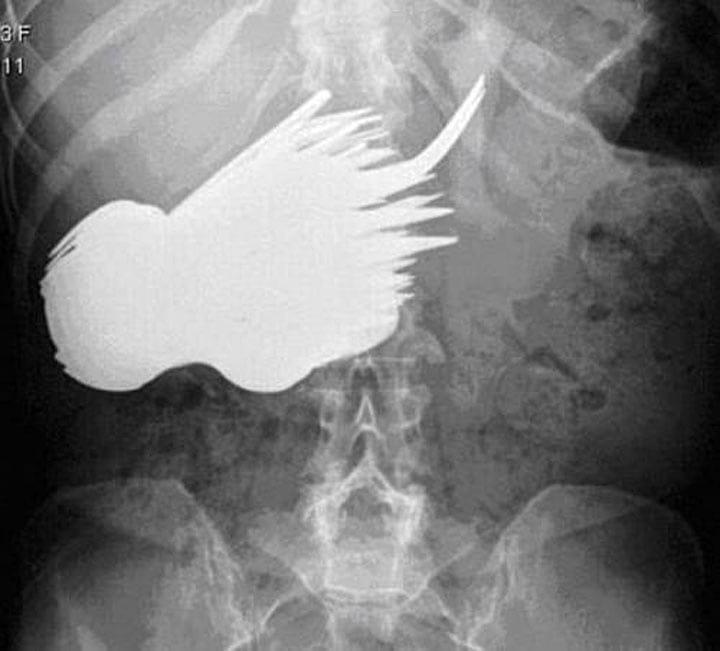

1. Эта женщина по неизвестным причинам проглотила 78 столовых приборов